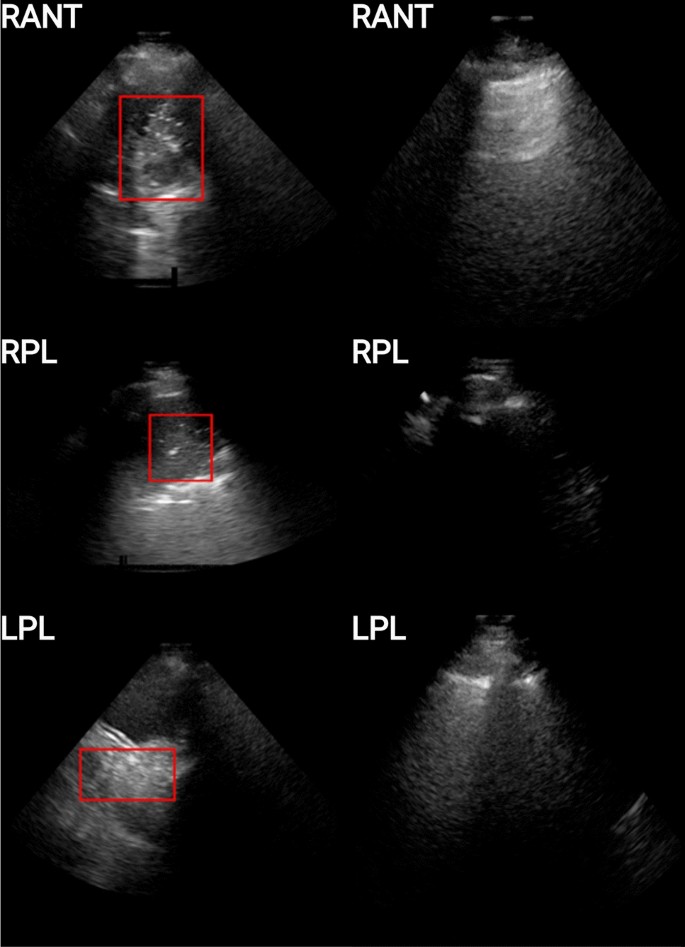

The original LUS image dataset consisted of 125 patients, it included a range of imaging patterns associated with multiple pathologies. Images were stored in DICOM format. The performing physician recorded the image interpretation on a standardized report form. Based on the available medical reports, we identified 46 patients with lungs of healthy appearance (healthy patients), and 11 patients with lungs of unhealthy appearance consisting of evidence of consolidation/collapse (unhealthy patients). These 11 unhealthy (consolidation/collapse) patients’ LUS images were screened by two independent experts in ultrasound (AW and MS) for image quality (Section 2: A1) and interpretation confidence (Section 2: A1). This resulted in the selection of 9 unhealthy consolidation/collapse patients. Eighteen healthy patients out of the 46 were then randomly selected for this study. A normal lung pattern was identified by the presence of lung sliding, reverberation artifacts from the pleura, and absence of atelectasis31 (collapse) or consolidation (Fig. 3). Distinguishing between lung atelectasis31 (collapse) and consolidation is challenging on lung ultrasound, as the two frequently co-exist. For this preliminary study, consolidation and atelectasis were considered as one finding (I.e. collapse/consolidation). Collapse/consolidation was defined as an area of increased tissue density (tissue pattern) in the lung space that has the appearance of a solid organ, such as the liver (‘hepatization’). Other features used to report the presence of collapse/consolidation include air bronchograms (hyperechoic dots) and loss of lung volume, however these were not strictly required. Figure 3 demonstrates comparison LUS frames of an unhealthy (consolidation/collapse) vs healthy patient, from three different scan protocol regions. Out of the total 6 regions scanned during the examination, in our dataset, the RANT, RPL, and LPL regions contained imaging patterns consistent with lung consolidation/collapse. This resulted in the frames per LUS video varying anywhere from 50 to 300 frames, and for multiple scans (1-5 videos) per region. The distribution of unhealthy (consolidation/collapse) and healthy patients in the dataset and any coexisting lung pattern changes that were identified are shown in Table 1 and Fig. 2.

Examples of unhealthy (left column) and healthy (right column) patients for 3 scanning regions (viz. RANT, RPL, LPL). The unhealthy patients are those for which consolidation is present, and are depicted here with a red bounding box encompassing the imaging patterns associated with the pathology, while the healthy patients are those for which no imaging patterns associated with consolidation/collapse or other pathologies.